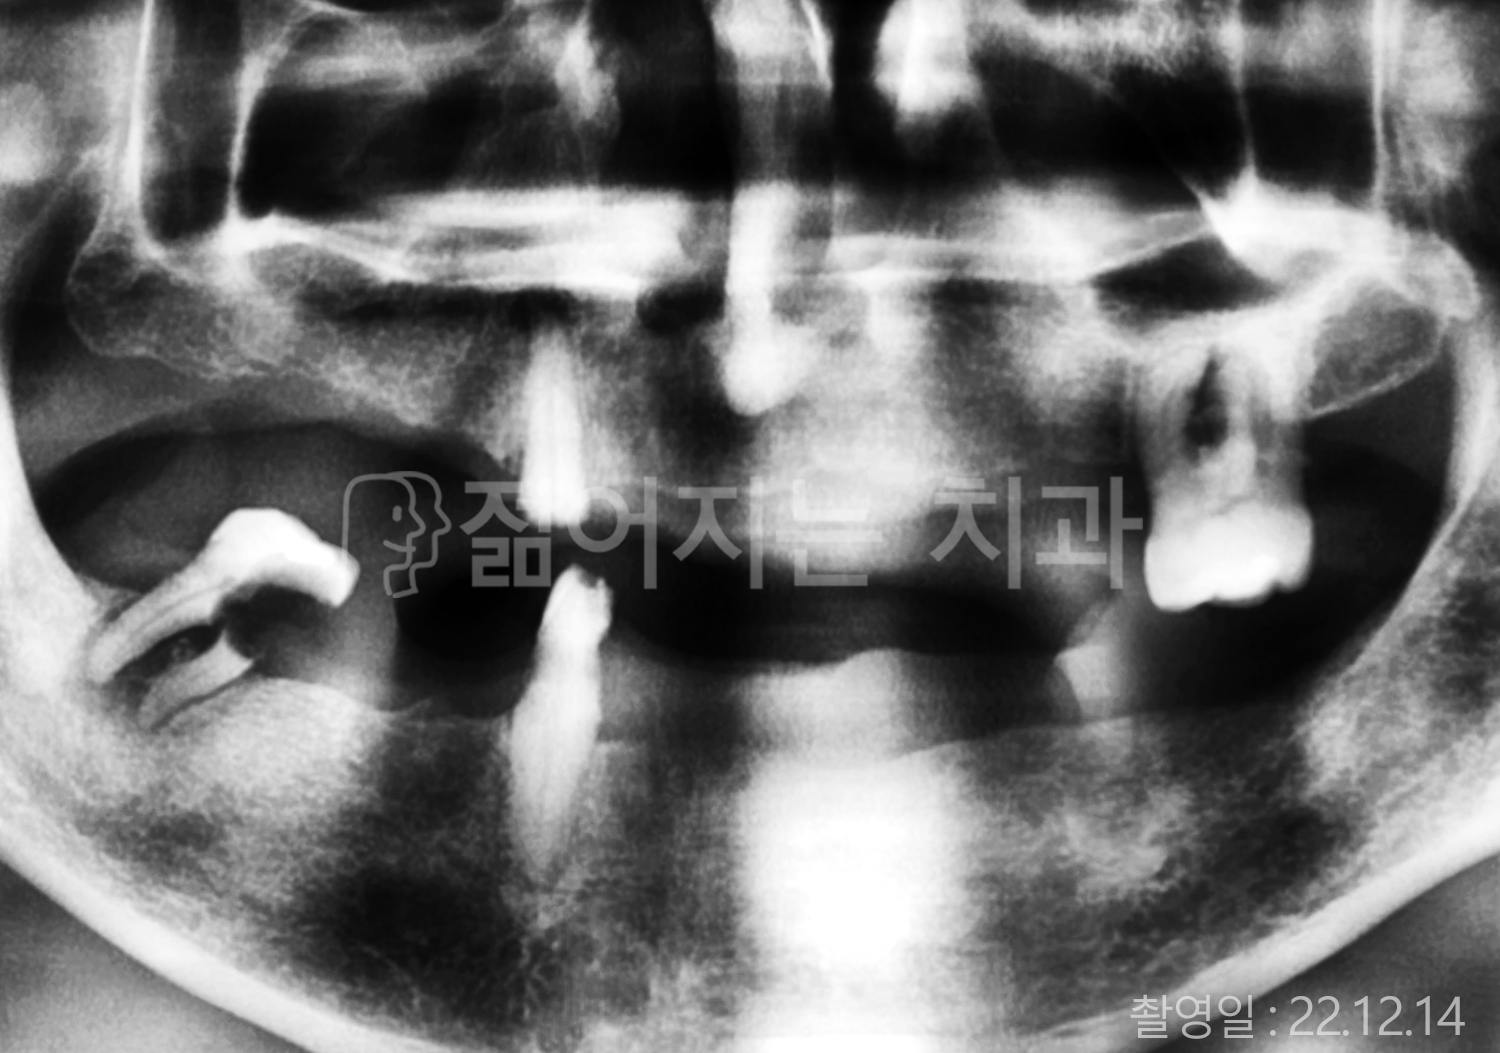

• 40대 전체치아 10개 이상 임플란트

• 50대 전체치아 10개 이상 임플란트

• 50대 고혈압, 당뇨, 고지혈증 전체치아 10개 이상 임플란트